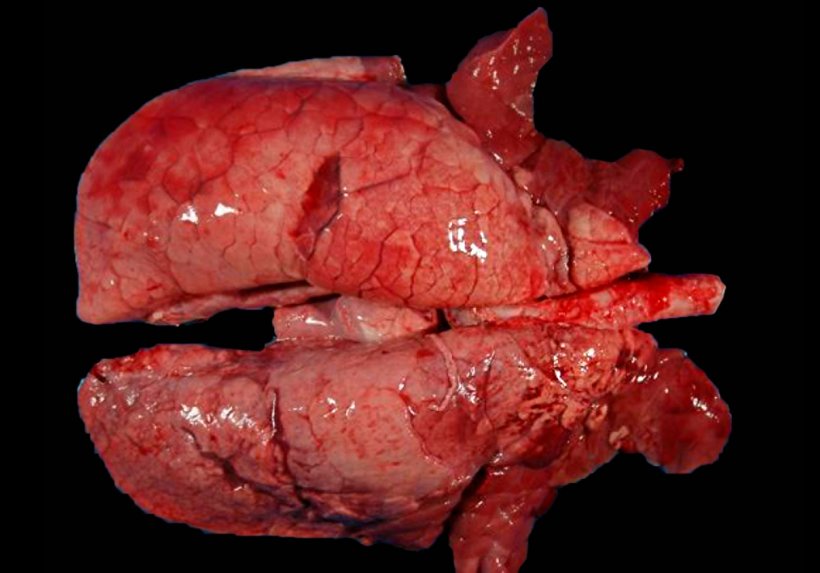

Eine der häufigsten Koinfektionen in Schweinehaltungsbetrieben mit Fällen von PRDC ist eine Koinfektion, die durch M. hyopneumoniae und PRRSV hervorgerufen wird (Abb. 2). In den Fällen, in denen diese Koinfektion diagnostiziert wurde, stellte man eine positive Korrelation zwischen den Tieren fest, die bezüglich jedes einzelnen der beiden Erreger seropositiv sind. Mit anderen Worten: Die meisten Tiere, die PRRSV-positiv sind, sind auch bezüglich M. hyopneumoniae positiv. Darüber hinaus wurde nachgewiesen, dass M. hyopneumoniae die durch PRRSV hervorgerufene Lungenentzündung verlängert und verstärkt, was darauf zurückzuführen sein könnte, dass bei Tieren, die mit beiden Erregern koinfiziert sind, eine Zunahme von pro-inflammatorischen Zytokinen wie IL1-β, IL-8 und TNF-α erfolgt, die die Entzündungsreaktion auf Lungenebene verstärken. Aber es gibt auch eine verstärkte Synthese von IL-10, einem entzündungshemmenden Zytokin, das die Produktion anderer Zytokine hemmt und reguliert und es ermöglichen würde, den Schaden auf Lungenebene aufrechtzuerhalten, indem es die Auslösung einer unkontrollierten Entzündungsreaktion verhindert. IL-10 ist auch in der Lage, die Immunantwort des Tieres zu modulieren, was zusammen mit der Aktivierung anderer Mechanismen die adaptive Immunantwort verändert und es dem Erreger möglich macht, in der Lunge längere Zeit Wirkung zu zeigen.

Abbildung 2: Mit M. hyopneumoniae und PRRSV koinfizierte Lunge eines Schweins. Nicht kollabierte Lunge mit rötlich-braunen Bereichen mit Läsionen, die über das Parenchym verteilt sind, typischen PRRS-Läsionen, die gleichzeitig rötliche konsolidierte Stellen in den kranioventralen Bereichen aufweisen, die durch die Infektion mit M. hyopneumoniae hervorgerufen wurden.